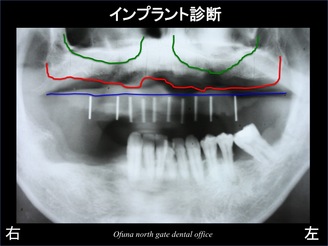

まず、初診時のレントゲン写真と見ながら解説していきます。

いつもと同じように骨吸収の状態を線で書いてみました。

青線が骨吸収を起こす前の骨の位置です。

赤線は、現在の骨の位置です。

骨が吸収してしまったのが分かるかと思います。

黄色線は、鼻腔です。

鼻の穴です。

緑線は上顎洞です。

上顎洞(緑線の上方)は空洞です。

骨ではなく、穴が開いているのです。

このレントゲン写真を見て、

『奥歯にはわりと骨吸収が少なく、骨の高さが残っている!』

と感じられたかもしれません。

そのとおりなのです。

上顎では、歯が1本も残っていませんが、わりと骨が しっかりしているのです。

このことから この方が歯を失った原因が予想できます。

もし、歯周病 や 歯根破折 が原因で歯を失った場合には、骨の吸収が起こっています。

また、下顎においても奥歯は骨吸収を起こしていますが、

前歯はわりと大丈夫です。

骨吸収が起こっていないのに歯がダメになる?

このようなケースでは、噛み合わせが原因の可能性が考えられます。